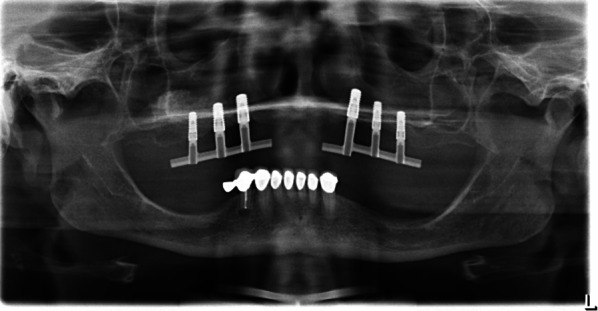

All patients received a prosthetic restoration (Figs. 6 and 7) on a bar-retained superstructure. Despite the loss of implants, all prosthetic restorations were functional until the end of follow-up according to the definition presented above.

Fig. 6.

Esthetic smile results of the upper denture

Fig. 7.

Panoramic X-ray of a bar-retained superstructure on six implants in the augmented maxilla (test: left side, control: right side)